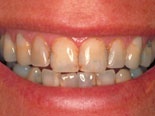

Före och efter behandling med kompositfasader.